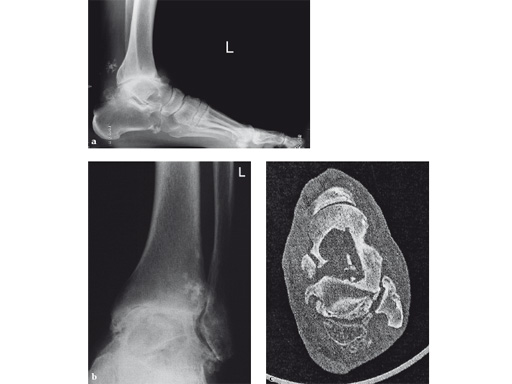

42-year-old, female with severe insulin-dependent diabetes mellitus (IDDM); Charcot foot, wheel chair since 1 year.

Case provided by Hermann Bail, Berlin, DE